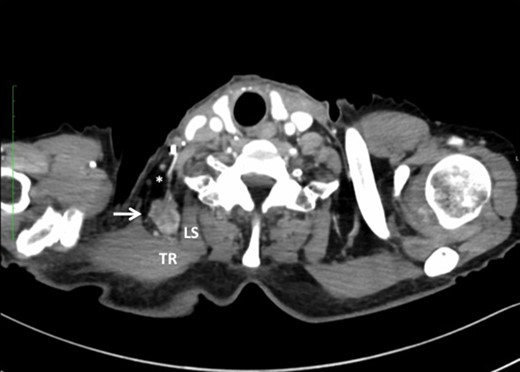

Metastasis of the supraclavicular nodes (SCNM), the nodes located between TR and LS (arrow) (A), and the axillary nodes (ANM) (B) developed 4 months after esophagectomy.

One possible explanation of this phenomenon is retrograde spread from SCNM. Komatsu et al. [3] reported four cases of axillary node metastasis (ANM) of squamous cell carcinoma of the upper- and mid-thoracic esophagus. All ANM developed on the left side, with the preceding or simultaneous left SCNM. The supraclavicular nodes are well known as regional lymph nodes in breast cancer, and lymphatics from the axillary nodes are considered to communicate with the supraclavicular nodes. Based on experimental and clinical observations, they concluded that ANM might be caused by retrograde flow owing to lymphatic blockade by SCNM in esophageal cancer [3, 4]. A similar mechanism was speculated in our cases 1 and 2, in which preceding or simultaneous ipsilateral SCNM also developed. Interestingly, simultaneous ANM was also seen in case 2.